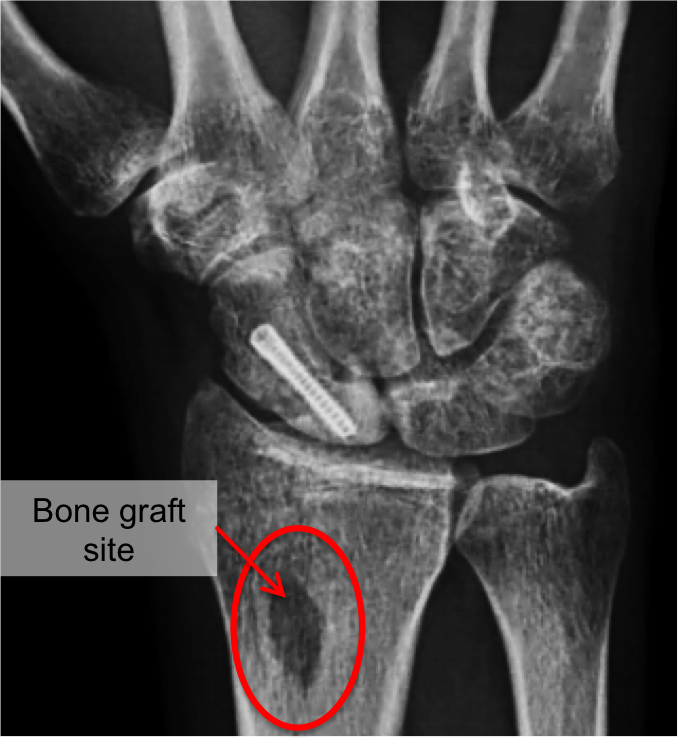

Scaphoid Fracture Of The Wrist Orthoinfo Aaos

Scaphoid Fracture Of The Wrist Orthoinfo Aaos from orthoinfo.aaos.org